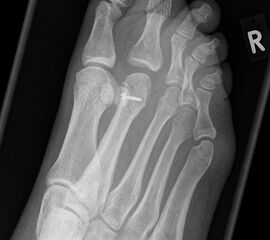

Vorfuß dorsoplantar (dp)

Positionierung:

• Patient liegt auf dem Rücken, der Fuß wird auf die Röntgenkassette aufgestellt, das Knie gebeugt.

• Der Zentralstrahl wird auf das Tarsometatarsalgelenk II zentriert.

• Die Röntgenröhre ist 15° vertikal gekippt.

• Anmerkung: Auch wenn der Fuß nicht belastet wird, sollte er auf die Röntgenkassette aufgestellt werden. Aufnahmen des hängenden Fußes sind nur eingeschränkt beurteilbar.

Kennzeichen des Röntgenbildes:

• Dorsoplantare Abbildung des Vorfußes.

• Tarometatarsale Gelenkreihe einsehbar.

• Winkelmaße können auf der unbelasteten Aufnahme des Vorfußes nicht beurteilt werden.

Besondere Bemerkungen zum Beispielbild:

• Verlaufskontrolle nach korrigierendem Vorfußeingriff bei Riesenwuchs des 2. Strahls mit verdicktem Os metatarsale II.

• Z.n. Amputation des Zehenendglieds D2.

• Z.n. Weil Osteotomie des Os metatarsale II.

• Hallux valgus interphalangeus.

Zur Vollansicht und zum Lesen der Bildbeschreibung bitte die Bilder anklicken.